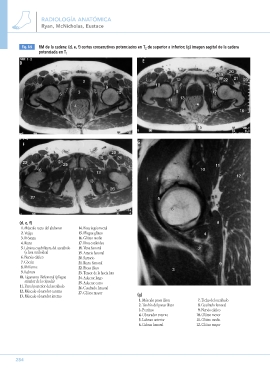

Fig. 8.9 RM de la cadera: (d, e, f) cortes consecutivos potenciados en T2 de superior a inferior; (g) imagen sagital de la cadera

potenciada en T1

27 1. Músculo psoas ilíaco

2. Tendón del psoas ilíaco

(d, e, f) 14. Fosa isquiorrectal 3. Pectíneo 8

1. Músculo recto del abdomen 15. Pliegue glúteo 4. Obturador externo 4

2. Vejiga 16. Glúteo medio 5. Labrum anterior

3. Próstata 17. Fosa cotiloidea 6. Cabeza femoral 2

4. Recto 18. Vena femoral

5. Lámina cuadrilátera del acetábulo 19. Arteria femoral 9

20. Sartorio

(y fosa cotiloidea) 21. Recto femoral 7. Techo del acetábulo

6. Nervio ciático 22. Psoas ilíaco 8. Cuadrado femoral

7. Cóccix 23. Tensor de la fascia lata 9. Nervio ciático

8. Piriforme 24. Aductor largo 10. Glúteo menor

9. Labrum 25. Aductor corto 11. Glúteo medio

10. Ligamento iliofemoral (pliegue 26. Cuadrado femoral 12. Glúteo mayor

27. Glúteo mayor

anterior de la cápsula)

11. Pared posterior del acetábulo

12. Músculo obturador externo

13. Músculo obturador interno